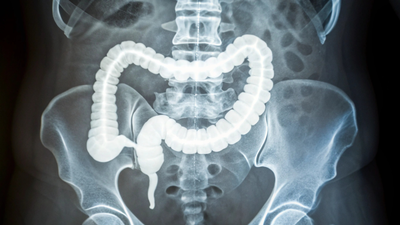

பெருங்குடல் புற்றுநோயானது முதுமையின் ஒரு நோயாகக் கருதப்படுகிறது, இது பெரும்பாலும் 50 வயதிற்குப் பிறகு தாக்குகிறது, ஆனால் கடந்த சில தசாப்தங்களாக, கொலோனோஸ்கோபி போன்ற பரவலான ஸ்கிரீனிங்கின் காரணமாக அந்தக் குழுவில் வழக்குகள் மற்றும் இறப்புகள் குறைந்துவிட்டன. ஆனால் இப்போது – 50 வயதிற்கு முன்பே தாக்கும் ஆரம்பகால பெருங்குடல் புற்றுநோய், 2020 முதல் அமெரிக்காவில் கண்டறியப்பட்ட அனைத்து நோயறிதல்களிலும் சுமார் 12% ஆகும். விகிதங்கள் கடுமையாக உயர்ந்துள்ளன, எந்த ஒரு குற்றவாளியும் இதுவரை முழுமையாக விளக்கப்படவில்லை.பலர் நவீன வாழ்க்கை முறைகளை சுட்டிக்காட்டுகின்றனர்: பதப்படுத்தப்பட்ட உணவுகளில் அதிக அளவு உணவுகள், நடுப்பகுதியில் கூடுதல் பவுண்டுகள் மற்றும் காலப்போக்கில் குடலை எரிச்சலடையச் செய்யும் சுற்றுச்சூழல் காரணிகள். இந்த நாள்பட்ட வீக்கம் உடனடி வலியை ஏற்படுத்தாது, ஆனால் அமைதியாக உருவாகிறது – பிரச்சனைக்கு மேடை அமைக்கிறது. 2030 ஆம் ஆண்டளவில் இந்த எண்கள் இரட்டிப்பாகும் என்று கணிப்புகள் தெரிவிக்கின்றன, குறிப்பாக 20 முதல் 40 வயதிற்குட்பட்டவர்களிடையே, சோதனைகளை எப்போது தொடங்குவது என்பதை மருத்துவர்களை மறுபரிசீலனை செய்யத் தூண்டுகிறது.

ஒரு சமீபத்திய ஆய்வில், இளமைப் பருவத்தில் பெருங்குடல் புற்றுநோய் ஏன் அடிக்கடி ஏற்படுகிறது என்பதை வெளிச்சம் போட்டுக் காட்டுகிறது, இது ஒரு கடினமான பெருங்குடலைச் சுட்டிக்காட்டுகிறது. பல ஆண்டுகளாக குறைந்த தர வீக்கத்தால் இயக்கப்படுகிறது – இந்த திசு கடினப்படுத்துதல் கட்டிகளை பிடித்து வேகமாக வளர சரியான புயலை உருவாக்குகிறது. இந்த கண்டுபிடிப்புகள் 50 வயதிற்குட்பட்டவர்களுக்கான சிறந்த ஸ்கிரீனிங் மற்றும் சிகிச்சைகளுக்கு கதவுகளைத் திறக்கும் என்று ஆராய்ச்சியின் பின்னால் உள்ள வல்லுநர்கள் நம்புகிறார்கள்.ஆரம்ப-தொடக்க மாதிரிகள் தனித்து நிற்கின்றன: ஒட்டுமொத்தமாக மிகவும் கடினமானவை. ஆழமாக தோண்டிய குழு, தடிமனான, நீளமான கொலாஜனின் இழைகளைக் கண்டறிந்தது, இது வடுவின் போது உருவாகும் புரதமாகும். இந்த கொலாஜன் மிகவும் முதிர்ச்சியடைந்தது மற்றும் நேர்த்தியாக சீரமைக்கப்பட்டது, மீண்டும் மீண்டும் அழற்சியின் அடையாளங்கள் அதன் அடையாளத்தை விட்டு வெளியேறுகின்றன. மரபணு சோதனைகள் அதை உறுதிப்படுத்தியது, கொலாஜன் செயலாக்கம், புதிய இரத்த நாளங்களின் வளர்ச்சி மற்றும் இளைய நோயாளிகளின் திசுக்களில் நடந்துகொண்டிருக்கும் நோயெதிர்ப்பு மறுமொழிகளுக்கான விரைவான-அப் செயல்பாட்டைக் காட்டுகிறது.

இங்கே அது கவர்ச்சிகரமானதாக இருக்கிறது. குடலில் நாள்பட்ட எரிச்சல், மார்பக அல்லது கணையப் புற்றுநோய்களில் நடப்பதைப் போன்றே, பெருங்குடல் சுவர்களை இறுக்கமாக்கும் வடுக்களை ஏற்படுத்துகிறது. செல்கள் இதைப் புறக்கணிப்பதில்லை; மெக்கானோட்ரான்ஸ்டக்ஷன் எனப்படும் ஒரு செயல்முறையின் மூலம் அவர்கள் அழுத்துவதை உணர்கிறார்கள். மெக்கானிக்கல் ஸ்ட்ரெஸ் செல்களுக்குள் சுவிட்சுகளை புரட்டுகிறது, உயிர்வேதியியல் சமிக்ஞைகளைத் தூண்டுகிறது, அவை அவற்றைப் பிரிக்கவும் பரவவும் சொல்கிறது.புள்ளியை நிரூபிக்க, விஞ்ஞானிகள் பல்வேறு கடினத்தன்மை நிலைகளை பிரதிபலிக்கும் பரப்புகளில் பெருங்குடல் புற்றுநோய் செல்களை வளர்த்தனர். கடினமானவற்றில், செல்கள் வேகமாகப் பெருகும். அவர்கள் நோயாளி உயிரணுக்களிலிருந்து 3D ஆர்கனாய்டுகளை-மினி கட்டி மாதிரிகளை உருவாக்கினர், மேலும் திடமான தளங்களில் உள்ளவை பெரியதாகவும் வேகமாகவும் பலூன் செய்யப்பட்டன. இது ஒரு கடினமான சூழல் புற்றுநோய் செழித்து வளர அனுமதிக்காது என்று தெரிவிக்கிறது; இது சாதாரண செல்களை முதலில் வீரியம் மிக்க தன்மையை நோக்கி தள்ளும்.